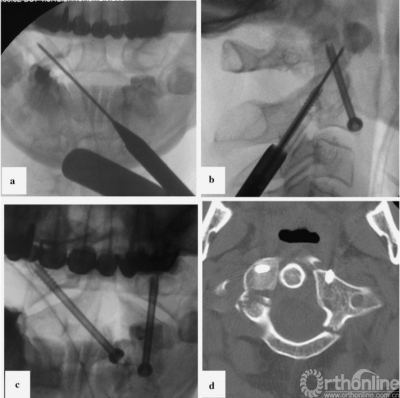

最初,我们计划使用Harms技术进行C1-C2固定,用螺钉将寰椎碎裂的侧块融合。然而,病人的解剖特征使得这一方法不可行:其椎动脉位于C2椎体右侧,使右侧无法进行关节融合术。而C2右椎弓根、峡部、弧形部体积小,也使C1-C2的后路螺钉固定技术无法实施(图1,右侧)。由于这些限制,我们采用了前路经寰枢关节交叉螺钉固定技术(图2)和后路的Magerl技术[7]。

图2前路经C1-C2关节螺钉固定术中螺钉插入对侧轨迹示意图:正位视图(左)和侧位视图(右)

A 50-year-old man was admitted to our department in May 2014 after a car accident. Cervical spine computed tomography (CT) scans revealed multiple fractures in the anterior and posterior arcs of the atlas and abruption of the posterior third of its lateral mass (Fig.1,left). Clinical symptoms included severe cervical pain that increased dramatically when the patient moved his head; otherwise, he was neurologically intact. The concomitant traumatic brain injury, linear fracture of the left frontal and temporal bones, and soft tissue wound on the head prevented us from using the Halo device for an extended period of time. Initially, we planned to perform C1-C2 fixation using the Harms technique and fusion of the shattered lateral mass of the atlas with a screw. However, the patient’s anatomical characteristics prevented this. The location of the vertebral artery on the right side of the C2 vertebra made it impossible to perform transarticular fusion on that side. The small size of the C2 right pedicle, pars interarticularis, and arc also made it impossible to use the posterior screw fixation technique of C1–C2 on the right side (Fig.1,right). Due to these limitations, the combined anteroposterior atlantoaxial fixation technique with contralateral screw insertion (Fig.2) and Magerl trajectory[7]was performed.

Fig. 2 Schematic representation of the contralateral trajectories of screw insertion during anterior transarticular fixation of C1–C2. Anteroposterior (left figure) and lateral (right figure) views are shown here